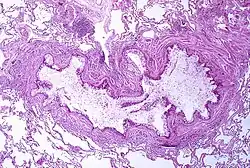

Pathophysiology

Asthma is the result of chronic inflammation of the conducting zone of the airways (most especially the bronchi and bronchioles), which subsequently results in increased contractability of the surrounding smooth muscles.[21] This among other factors leads to bouts of narrowing of the airway and the classic symptoms of wheezing. The narrowing is typically reversible with or without treatment. Occasionally, the airways themselves change.[21] Typical changes in the airways include an increase in eosinophils and thickening of the lamina reticularis.[20] Chronically, the airways' smooth muscle may increase in size along with an increase in the number of mucous glands.[20] Other cell types involved include T lymphocytes, macrophages, and neutrophils. There may also be involvement of other components of the immune system, including cytokines, chemokines, histamine, and leukotrienes among others.[20]